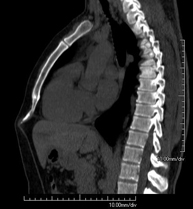

- Abdominal and pelvic CT

Diagnostic test that consists of obtaining high-definition anatomical images (bone structures, vascular structures, liver, pancreas, gallbladder, kidneys, adrenal glands, spleen, small and large intestine, bladder, uterus and ovaries, prostate and seminal vesicles, ureters, etc.) using CT (computed tomography) equipment. Most studies require the use of iodinated contrast.